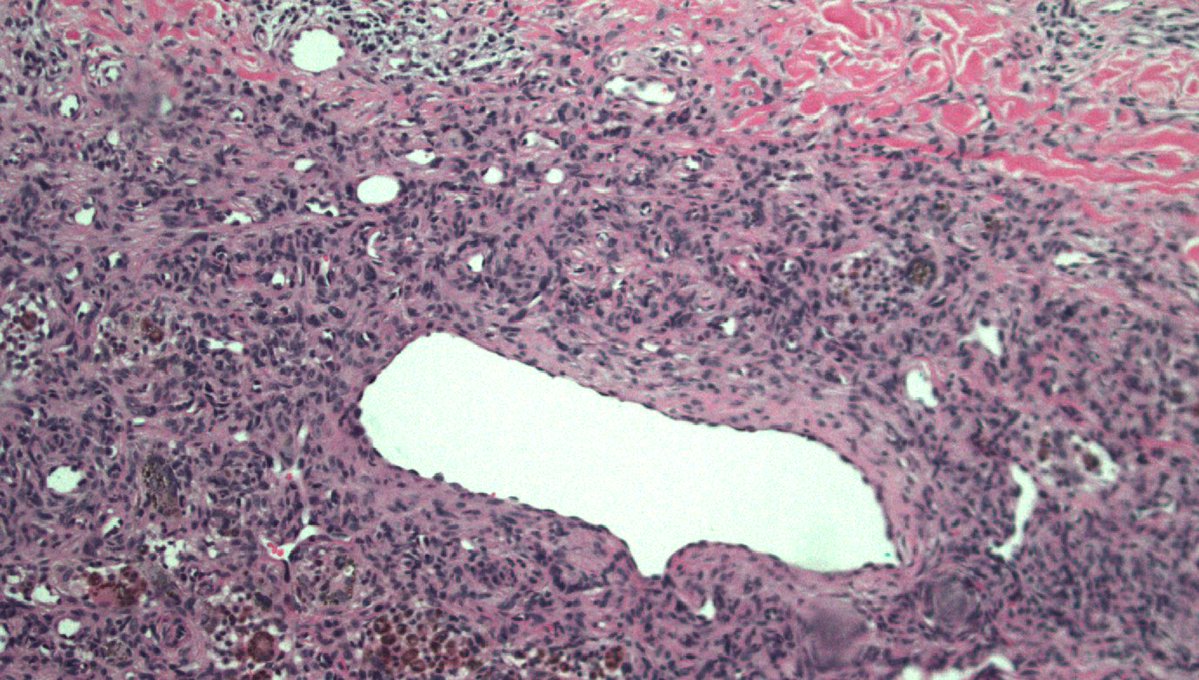

40 F. 10 cm deep thigh mass.

Answer ✅ youtu.be/QDb68_G1HR4?si…

Digital slide 🔬 kikoxp.com/posts/11800.

Differential dx: kikoxp.com/posts/12124

#BSTpath #pathologists #pathology #pathTwitter